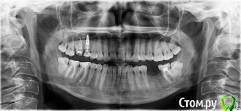

Весна2009 Опубликовано 30 января, 2017 Автор Поделиться Опубликовано 30 января, 2017 В день установки импланта Ссылка на комментарий

red_butler Опубликовано 31 января, 2017 Поделиться Опубликовано 31 января, 2017 В день установки импланта перезалейте через файлообменник Ссылка на комментарий

Весна2009 Опубликовано 31 января, 2017 Автор Поделиться Опубликовано 31 января, 2017 (изменено) http://s1.radikale.ru/uploads/2017/1/31/7d2d24c59e27de2de33677ab6475dad5-full.jpg http://s1.radikale.ru/uploads/2017/1/31/0cdd32751f158de955ad2a3d9ace2810-full.jpg http://s1.radikale.ru/uploads/2017/1/31/1f8cb5b134a47f7ffb376e14dd038406-full.jpg Изменено 31 января, 2017 пользователем Весна2009 Ссылка на комментарий